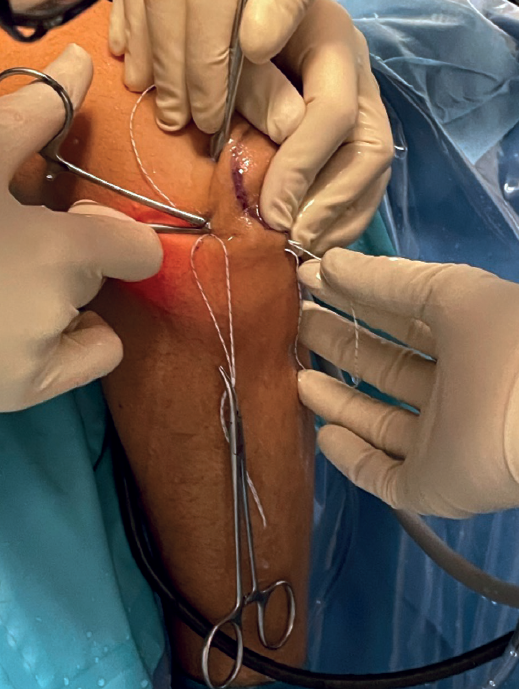

At this point we will have two sutures exiting through the soft spot; we will knot them together (Figure 4) to recover them by pulling on the suture located at the origin of the LCL. In this way we will have a single intra-articular suture extending from the insertion to the origin of the LCL, exiting through the skin in both places (Figure 5).